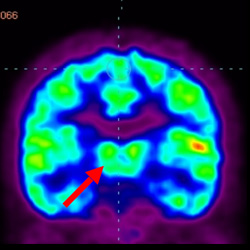

細胞治療前 PET CT 掃描顯示神經(jīng)組織中的藍/黑色區域,表明腦癱引起的大腦損傷。

腦癱細胞療法, 腦癱治療

細胞治療后,藍色和黑色區域減少,并且看到更活躍的區域。這表明損傷減少并改善了大腦功能。

這證明細胞療法是治療腦癱兒童安全有效的方法。細胞療法可以更新大腦損傷的核心,并且可以通過(guò) PET CT 掃描來(lái)監測大腦的改善情況。這些細胞療法與標準治療一起促進(jìn)腦癱兒童的生長(cháng)和改善。